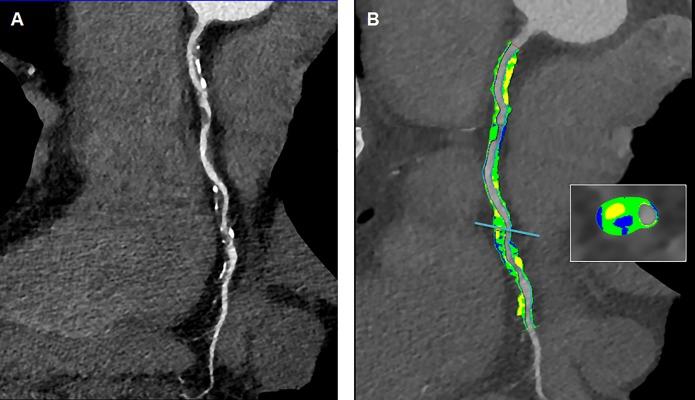

Circulating biomarkers available in clinical practice do not allow to stratify patients with coronary heart disease (CHD) prior the onset of a clinically relevant event. We evaluated the methylation status of specific genomic segments and gene expression in peripheral blood of patients undergoing Cardiac Computed Tomography (CCT) for CHD (n = 95). We choose to investigate cholesterol metabolism. Methylation and gene expression of low density lipoprotein receptor (LDLR), sterol regulatory element-binding factor 2 (SREBF2) and ATP-binding cassette transporter 1 (ABCA1) were evaluated by qRT-PCR. Calcium score (CACS), stenosis degree, total plaque volume (TPV), calcified plaque volume (CPV), non-calcified plaque volume (NCPV) and plaque burden (PB) were assessed in all CHD patients (n = 65). The percentage of methylation at the specific analyzed segment of LDLR promoter was higher in CHD patients vs healthy subjects (HS) (n = 30) (p = 0.001). LDLR, SREBF2 and ABCA1 mRNAs were up-regulated in CHD patients vs HS (p = 0.02; p = 0.019; p = 0.008). SREBF2 was overexpressed in patients with coronary stenosis ≥50% vs subjects with stenosis <50% (p = 0.036). After adjustment for risk factors and clinical features, ABCA1 (p = 0.005) and SREBF2 (p = 0.010) gene expression were identified as independent predictors of CHD and severity. ROC curve analysis revealed a good performance of ABCA1 on predicting CHD (AUC = 0.768; p<0.001) and of SREBF2 for the prediction of disease severity (AUC = 0.815; p<0.001). Moreover, adjusted multivariate analysis demonstrated SREBF2 as independent predictor of CPV, NCPV and TPV (p = 0.022; p = 0.002 and p = 0.006) and ABCA1 as independent predictor of NCPV and TPV (p = 0.002 and p = 0.013). CHD presence and characteristics are related to selected circulating transcriptional and epigenetic-sensitive biomarkers linked to cholesterol pathway. More extensive analysis of CHD phenotypes and circulating biomarkers might improve and personalize cardiovascular risk stratification in the clinical settings.